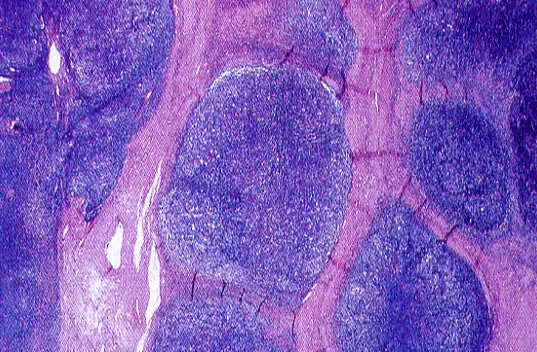

從提供的 H&E 染色淋巴結切片可見:

- 淋巴結皮質及皮質下被清晰的粉紅色纖維束分隔成多個大小不一的圓形結節(nodular architecture),纖維束呈厚實並可見 birefringent 特性,顯示活躍的結締組織增生。

- 在各結節間、結節中央可見細胞群聚,細胞質留有「空泡狀凹窩」(lacuna-like space),其中蘊含 Reed–Sternberg variants,即 lacunar cells。

- 未見散在巨量炎性細胞以 eosinophil、neutrophil 為主的混雜背景,也無全片廣泛弥漫性纖維化,顯示為結節狀、局部性的纖維化病灶。

這些影像特徵符合 Nodular sclerosis Hodgkin lymphoma(NSCHL)的典型組織學表現。